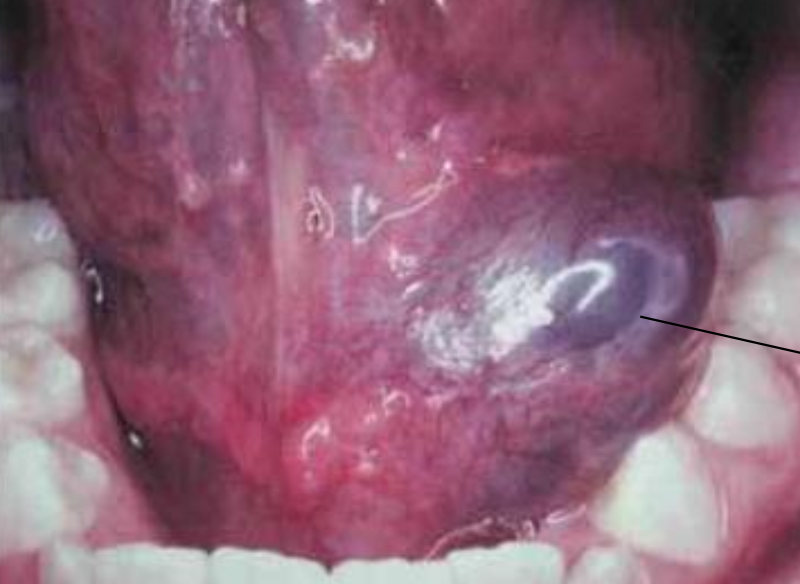

Excretory duct Mucoepidermoid carcinoma1st 2-70y

• parotid gland (60-70%) → Palate

Central type

• 最常見 intrabony salivary

• 來自齒源性上皮

• 大部分 low grade

• radiolucency